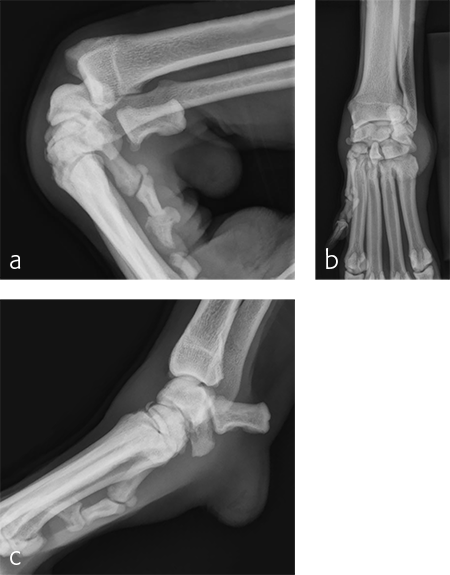

A 7-year-old, 32.5 kg, Labrador Retriever became acutely lame on the left thoracic limb while catching a ball. It was evaluated three weeks later and had carpal swelling, pain, and instability of the left carpus. Flexed lateral, craniocaudal, and extended mediolateral view images of the left carpus revealed a dorsal chip fracture at the carpometacarpal joint and hyperextension of the left carpus (Fig 9).